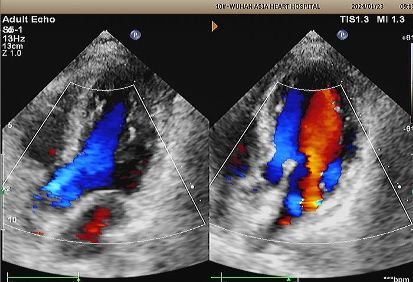

1 yıllık eko:

No visible disc structures – replaced by 8mm tissue thickening at the septal implant site.

Zero residual shunt (rest or post-Valsalva).

Komple cihaz emilimi onaylandı.